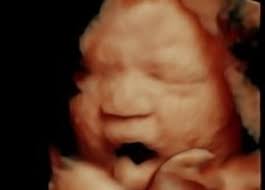

Sweet baby face louisville ky. March 1 2020. Sweet Baby Face is a 3D 4D Ultrasound and Baby Boutique in Louisville Elizabethtown KY. See your child in more depth and detail.

Pregnancy and Childbirth Service Near Sweet Baby Face. They give you a much clearer view of your child than the traditional 2D ultrasound you may even see if your baby has you or your partners features. Company Profile Contact information Current and former Employee directory Corporate history statetax IDs.

We do 2D 3D 4D HD5D elective ultrasound images in Louisville Elizabethtown. Millions of Products Top Brands. Combining cutting-edge technology with a spa theater environment we bring unbelievable images of your unborn baby to life.